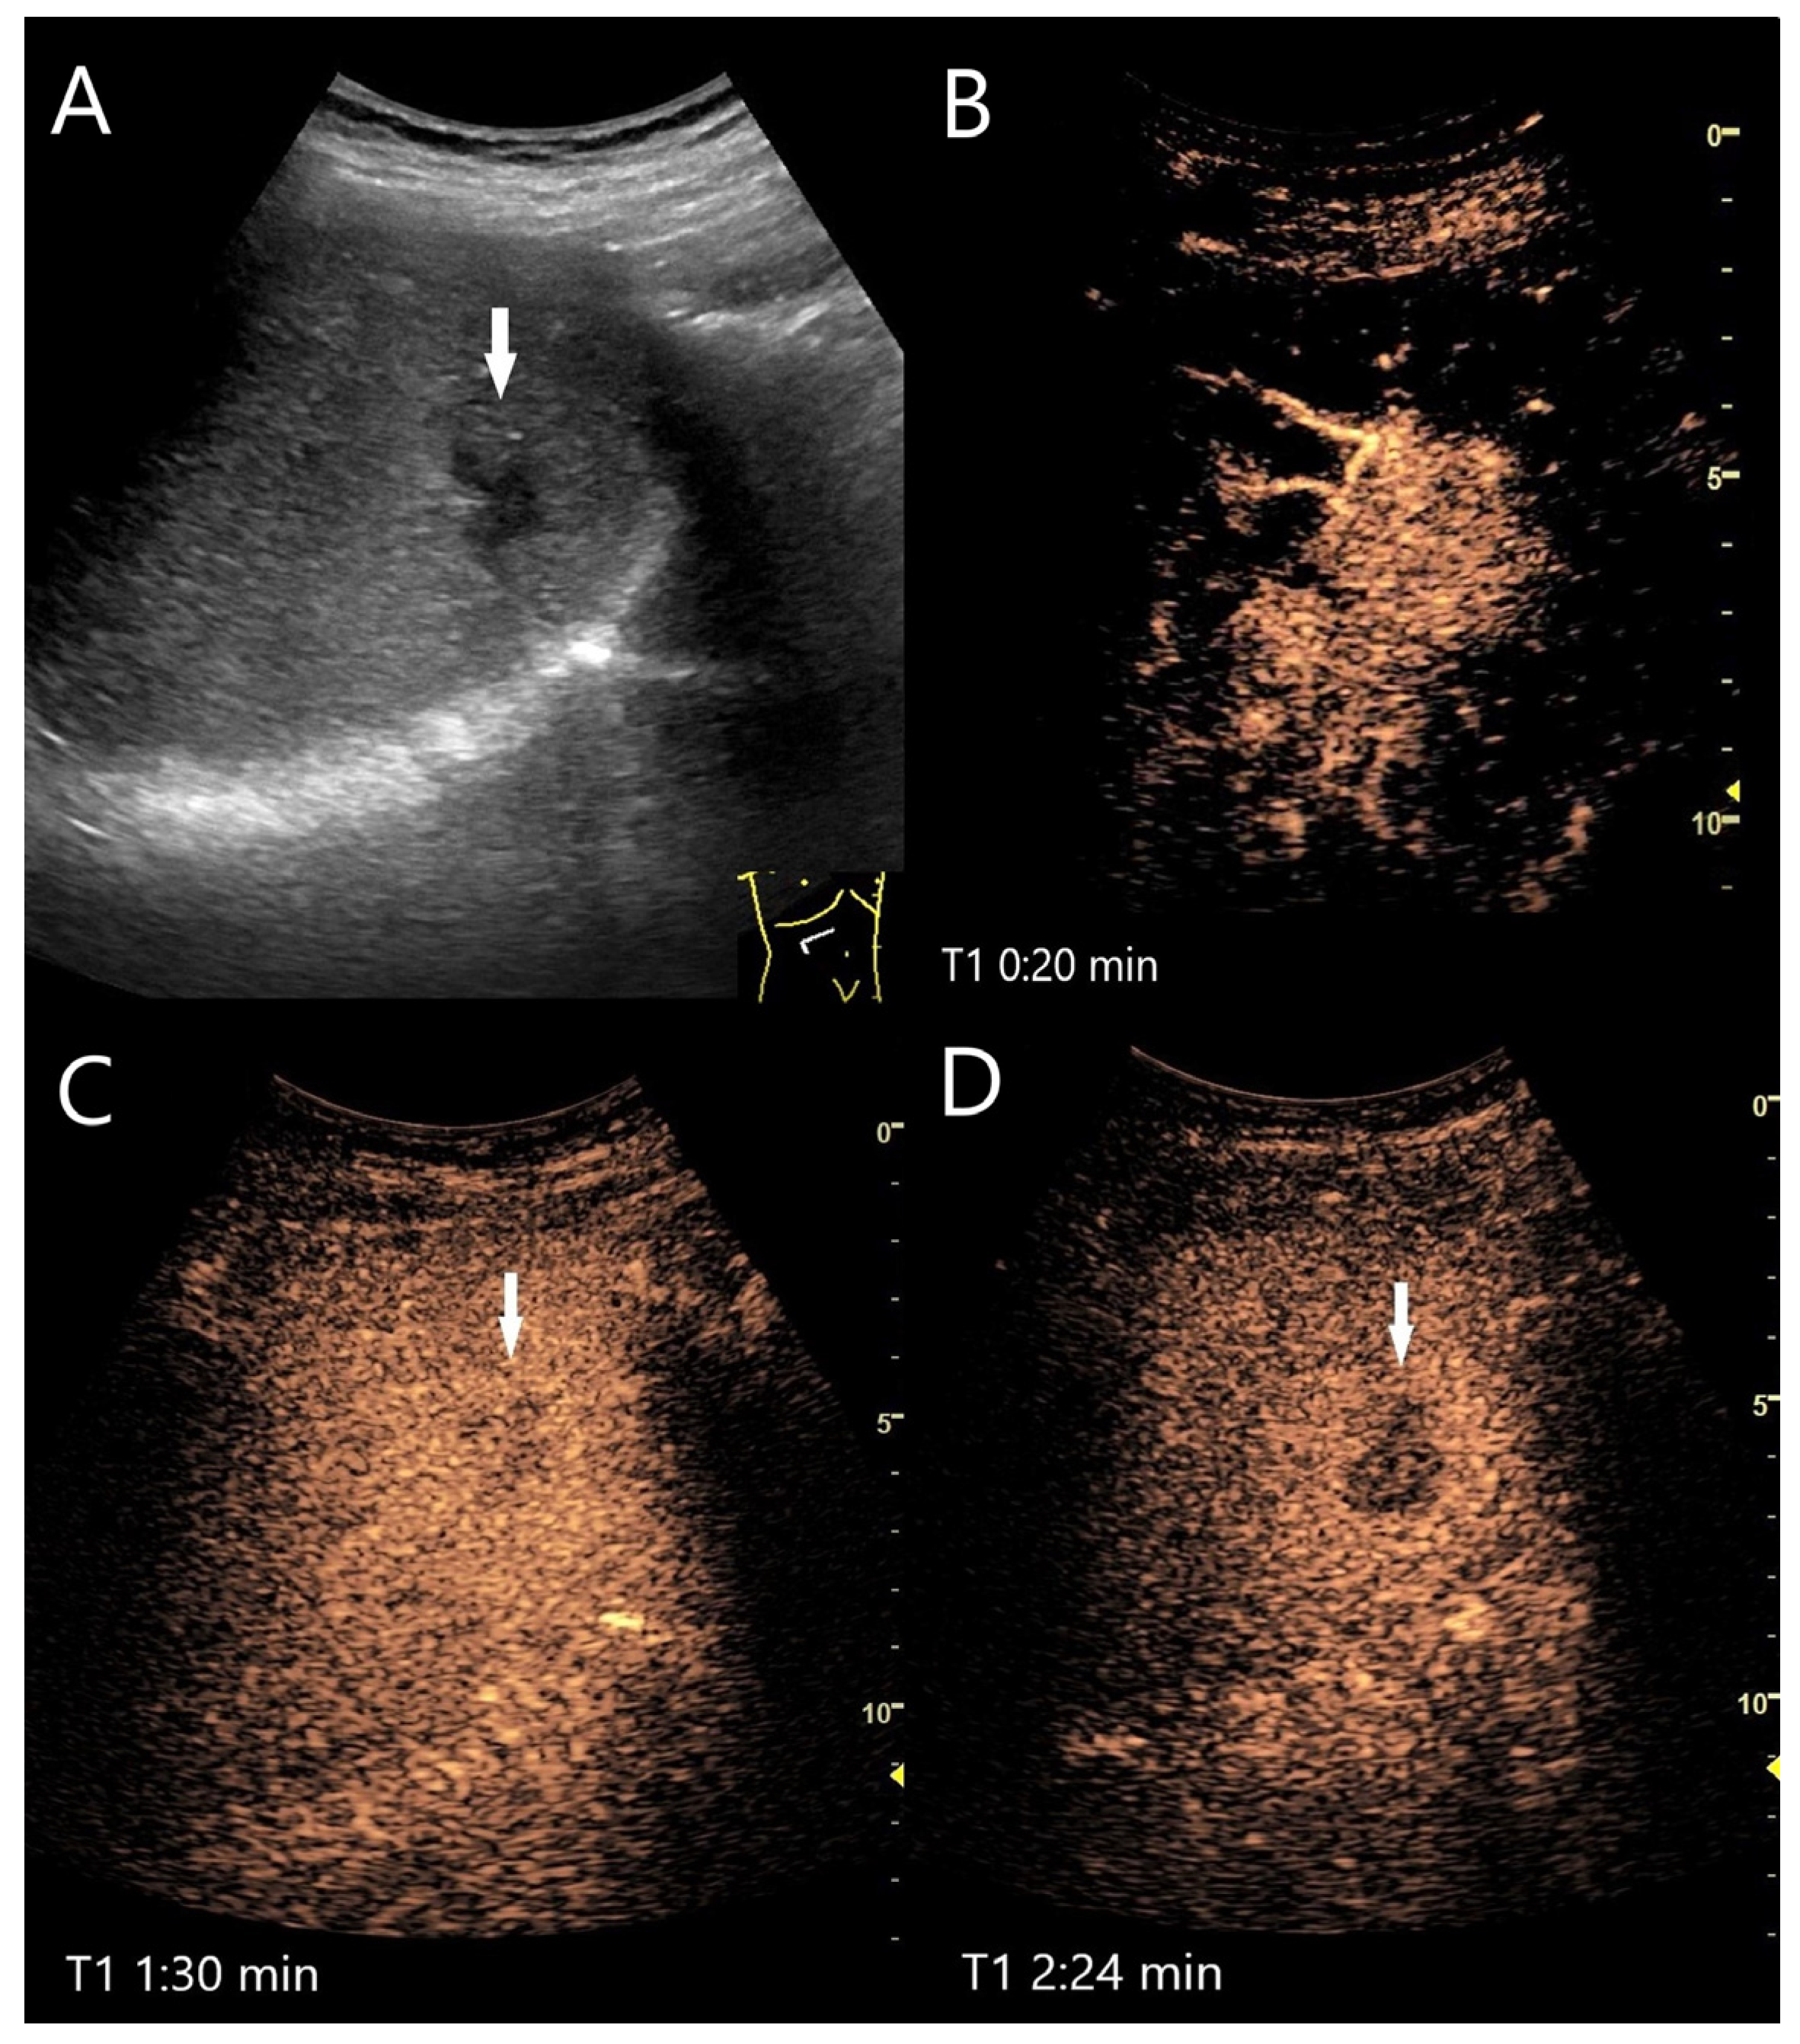

| FNH | Isoechoic, hypoechoic, sometimes hypoechoic rim. | Wheel spoke pattern, central artery, rarely peripheral artery and wheel. spoke pattern. Centrifugal filling | Hyperenhancement to isoenhanced, central scare. | Fibrosis and vascular obliteration. |